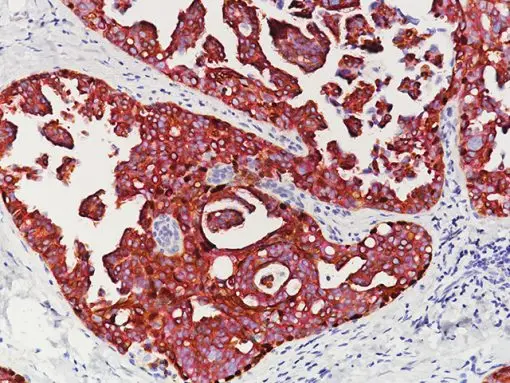

Breast Cocktail (CK HMW/p63 + CK7/8/18) is comprised of mouse monoclonal anti-CK HMW and anti-p63 antibodies as well as rabbit monoclonal anti-CK7 and mouse monoclonal anti-CK8/18 antibodies. CK HMW (high molecular weight cytokeratin) is expressed in the cytoplasm of basal cells and myoepithelium of breast tissue (1-4). p63 is a transcription factor present in the nuclei of myoepithelial cells (2,4). In contrast, CK7, CK8 and CK18 are low molecular weight cytokeratins primarily expressed in luminal cells of the breast (1-3).

CK HMW, p63, CK7, CK8 and CK18 have routinely been used as a panel of IHC markers to complement morphological evaluation in the assessment of breast lesions, due to the differential expression of the luminal vs. basal and myoepithelial markers (1-5). Cases of usual ductal hyperplasia (UDH) have been associated with expression of the basal cell markers, intermixed with cells expressing the keratins of luminal cells (1-2, 6-10). Most cases of atypical ductal hyperplasia (ADH) and low grade ductal carcinoma in situ (LG-DCIS) were negative for the basal markers and exhibited an immunophenotype indicative of luminal cells (1,5-8). Additionally, the basal phenotype has been shown to be characterized by luminal expression of the basal and myoepithelial markers, using a cocktail of CK HMW and p63 (11-13).